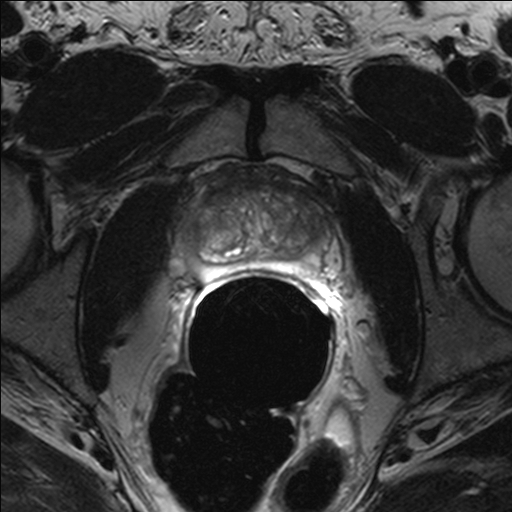

Magnetic Resonance Images

made at times June 18, 2007 and April 23, 2010 marked by left line near month 90 and line near month 124 in figures above

Transverse and coronal T2-weighted images were evaluated for hypointense regions in the peripheral zone of the prostate.

transverse T2-weighted image

T2-weighted transversal image #13 (total stack of layers: T2_tse_tra.mov)

Example MR images from a different patient

T2-weighted coronal image #11 (total stack of layers: T2_tse_cor.mov, T2_tse_cor.mp4)

(Gruber, Joachim: 07.04.1941 - Study: 14.07.46 - Time: 19:42:06 - Date 18/06/2007)

Findings 18. June 2007

Prostate as a whole is enlarged. The zonal structure is intact. The central zone is enlarged to a small extent as part of a BPH (Benign Prostate Hyperplasia).

In the peripheral zone the T2-weighted image showed low signal intensity areas

1. right laterally

2. left dorsobasally

In the T1-weighted image no signal-intense formations are delineable.

No indication of growth exceeding the capsula. No infiltration into the seminal bladders, the urinal bladder or the rectum. No indication of pathologially enlarged pelvic lymph nodes. Little free pelvic liquid.

Summary 18. June 2007

1. Together with a Benign Prostate Hyperplasia we find moderately cancer suspicious areas (grade 3 ... 4 on a scale from 1 (insignificant) to 6 (highly significant)). They show up

• (1) right laterally

• (2) left dorsobasally.

These might be targeted in a biopsy. No enlarged lymph nodes suspicious for metastasis.

2. Little free liquid, pelvic anamnesis?